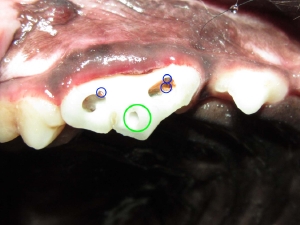

ヒトのような虫歯は大変少なく、通常は玩具による破折により生じた虫歯が大半をしめます。破折後8時間で「虫歯」となるために、できるかぎり早く病院へ行くことが大切です。遠方の方ではまずはお近くで抗生物質を処方していただくとよいでしょう。ヒトで歯医者にかかると、なにか口のなかをガリガリと削られ、そのあとに苦い薬をつけられて、1週間後に来院というイメージがあると思います。当日は、お口の中をみると虫歯の部位は、「白いかぶせ物」がしてあると思います。1週間後に再度、歯医者にかかると、そのかぶせ物をとられ、一部をインレーとよばれる「銀色の詰め物」をされると思います。ペットでも治療はなんら変わりません。異なる点といえば、虫歯の治療には必ず全身麻酔が必要になるという事です。簡単な虫歯であれば、ヒトと同様、虫歯部位を削り取り、詰め物をします。虫歯が深ければやはり神経を抜く(抜髄)という処置になります。当院では、クラウンダウン法という方法を用いておりますが、初回のアクセスを電動の低トルクエンジンで、その後は時と場合によりますが、ハンドファイルにてアクセスおよび治療していきます。ペットにもっとも生じるP4破折においては、3アクセスポイントがありますが、2つは非常にわかりやすいのですが、小型犬では3つ目のアクセスポイントが非常に難解なことがあります。アクセスポイントは光重合レジンで被覆し終了いたします。

青:アクセスポイント 緑:破折部位